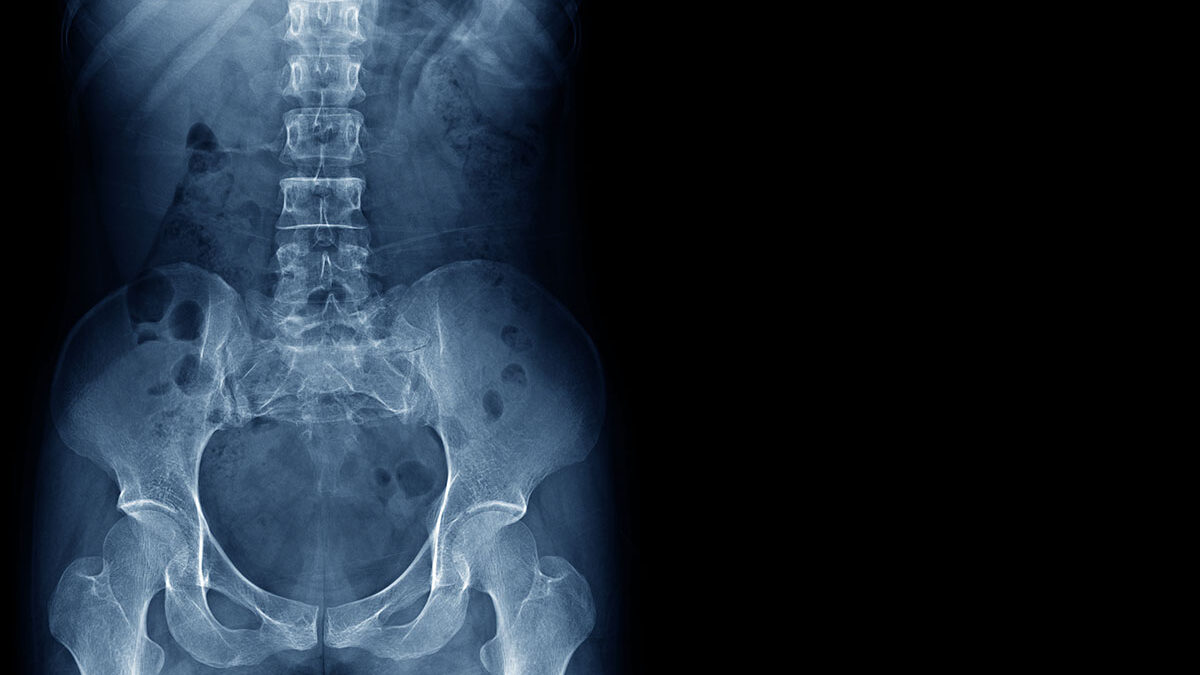

Imagine leaving a surgery center completely pain-free. The only sign that you received spinal surgery being a small bandage on your back. these are some of the aspects that make laser spine surgery so appealing to people living with chronic back pain in Florida.

If you have been told that you may need back surgery, It’s important to note that minimally invasive surgery using a laser isn’t a miracle cure and it isn’t viable for everybody. The laser assists in removing scar tissue, adhesions, and bone spurs in order to relieve back pain. This means that they can only be used for certain conditions.

This type of spine surgery gets its name, because the surgeon only needs to make a small incision in the back. After the incision has been made, specialized tools are used in order to provide the surgical team access to the affected area of the spine. Since no muscle dissection is needed with this type of surgery, there is less pain afterwards and recovery time is significantly shorter. Most minimally invasive spine surgeries can be done in an outpatient surgery center and patients can go home the same day.

During this procedure, our neurosurgeons use a laser to remove soft tissue that is compressing nerves (herniated discs and ligament enlargement). Remember that this type of application is only effective for specific conditions.

Lasers can be used to remove tumors from the spinal cord or to remove bone and soft tissue from around a nerve. This surgical tool is also great for removing disc material that is shrinking and compressing around the nerves. The surgeon uses a laser and an endoscopic camera to find the problem disc and remove the area that is causing your back pain.